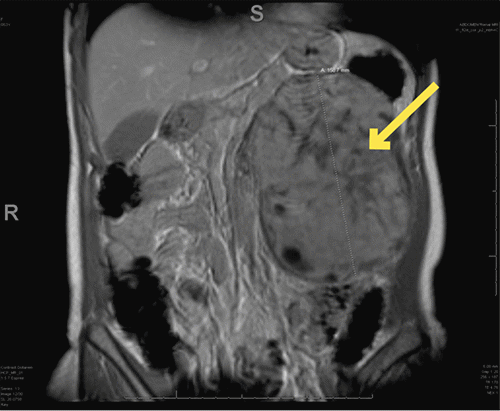

The patient is a 54-year-old woman who presented to the clinic with a one-year history of left-sided abdominal discomfort, fullness, and distension. She noted occasional constipation over the year but denied fevers, night sweats, unexpected weight loss, worsening fatigue, nausea, or vomiting. A palpable mass was appreciated on physical exam. Laboratory values on her complete blood count and comprehensive metabolic panel were unremarkable. Her primary care physician obtained an ultrasound demonstrating a heterogenous retroperitoneal mass measuring 15 cm × 9 cm × 14 cm arising from the left adrenal gland or left kidney. Subsequent magnetic resonance imaging of the abdomen performed at an outside institution (Figure 1) confirmed a 12 cm × 9 cm × 16 cm left-sided retroperitoneal mass displacing the left kidney and the pancreas. Although the mass was well-circumscribed, the origin of the mass was unclear. Intralesional regions of low intensity suggested central necrosis.

Figure 1. T1 Weighted MRI Images of Renal Leiomyoma in Axial. Published with Permission

A) Image depicting without intravenous contrast

B) Image depicting with intravenous contrast

C) Image depicting coronal at its largest dimensions